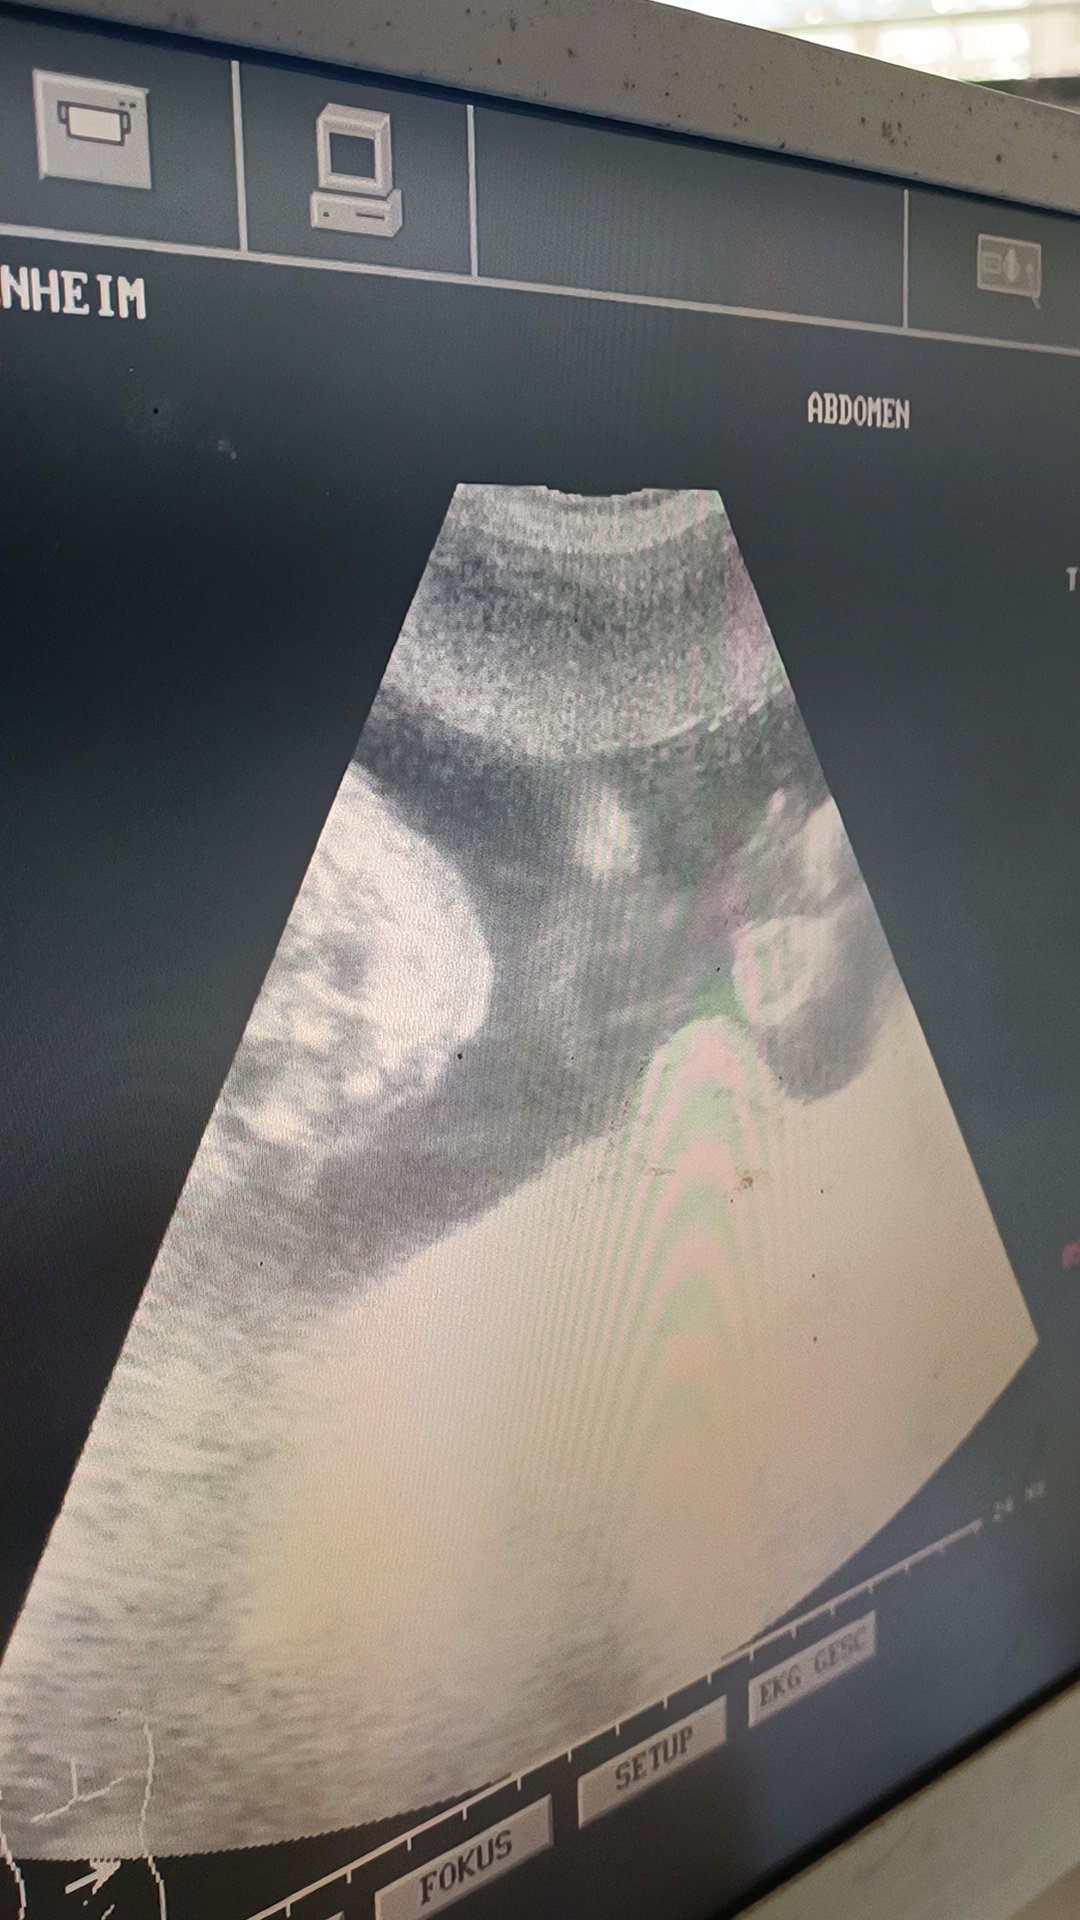

Als Highlight wurde noch ein Ultraschall für die Schwangeren angeboten:

Eine deutsche Hebamme, die immer wieder Teamtraining für Geburtshilfe macht, war wieder einmal in Kenia und hat die Ultraschalluntersuchungen bei den Frauen durchgeführt.